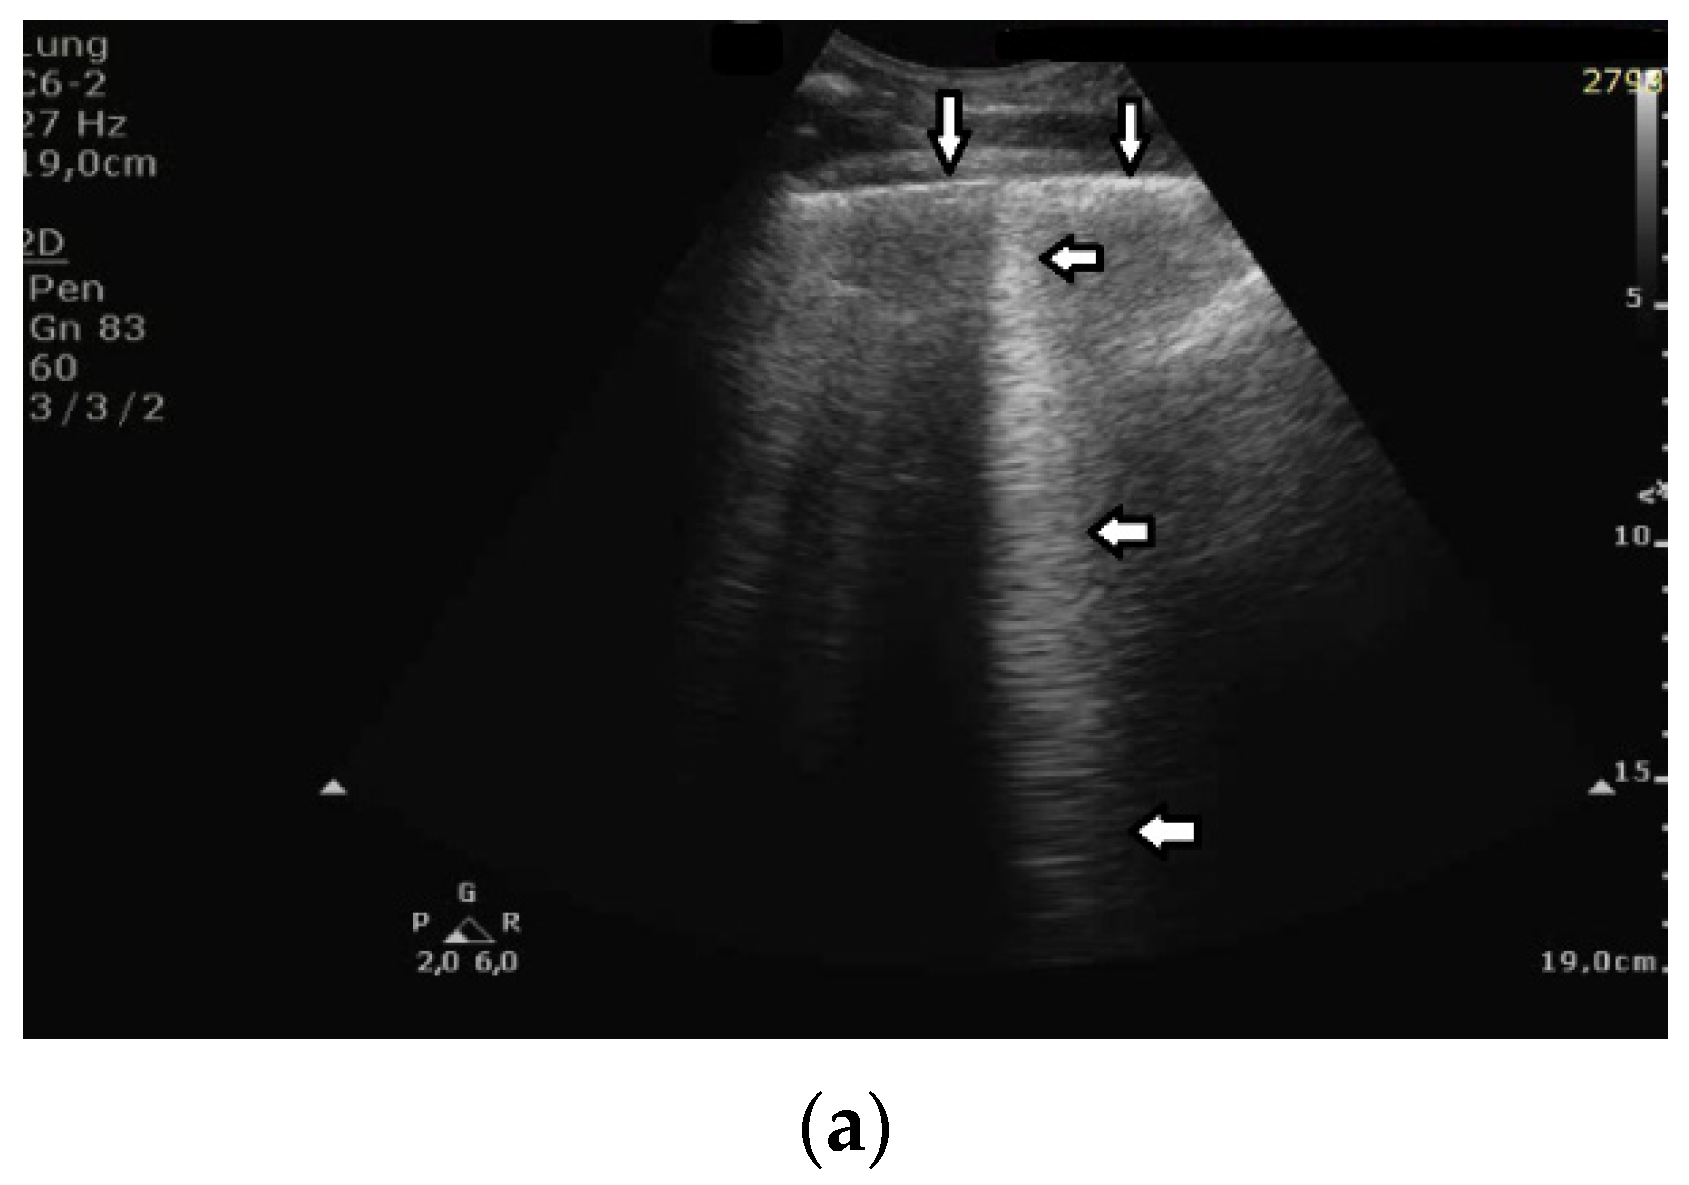

- Question 11:

The length of vertical artifacts can vary. Consistent with the terminology proposed by Daniel Lichtenstein, B, I, Z, and C lines are differentiated. B, Z, and I lines originate from the pleural line, but have various lengths. Thus far, Z and I lines have not been considered to be clinically significant. C lines originate from the lower edge of subpleural consolidations.

The significance of B lines is related to lesions affecting the interstitial space and alveoli (see Figure 6). Most frequently, the presence of B lines is reported in cardiogenic pulmonary edema, interstitial pneumonia, ARDS, and pulmonary fibrosis secondary to interstitial lung disease. Despite copious clinical observations describing the significance of B-line artifacts, we have still not acquired complete knowledge as regards their origin. The definition of a B line that is presently adopted is as follows:

Figure 6.

B lines (horizontal arrows) and pleural line (vertical arrows).

Do you agree with this definition of B line? Should we differentiate B lines from other vertical artifacts?

- Answer 11:

It is difficult to challenge a definition since a definition is a definition “by definition”. What I disagree with is the vagueness of this definition. “Moving with lung sliding” is a specific feature which links the artifact to a precise anatomical position of the outer lung surface where an acoustic trap developed. However, “well defined” is a subjective and vague characteristic. Moreover, the characteristic of “originating from the pleural line” is not properly formulated since in theory such a definition excludes B lines, which do not originate exactly at the pleural line. Due to both the size of the acoustic trap and the length of the linking acoustic channel, a B line often starts a bit lower than the pleural plane. “Going to the edge of the screen” is also an ambiguous characteristic since the edge of the screen is decided by the operator when he/she sets the acquisition depth. Even the characteristic of “Erasing A lines” is not properly formulated since some modulated B lines do not completely erase the A lines. In particular, the lateral size of B lines does not change a lot when a linear probe is used, and A lines mostly remain visible in the presence of a few B lines. Moreover, “laser like” is an intuitive description, but it is not specific. “Lying on the direction of the acoustic beam propagation” should be used since this is the specific characteristic.